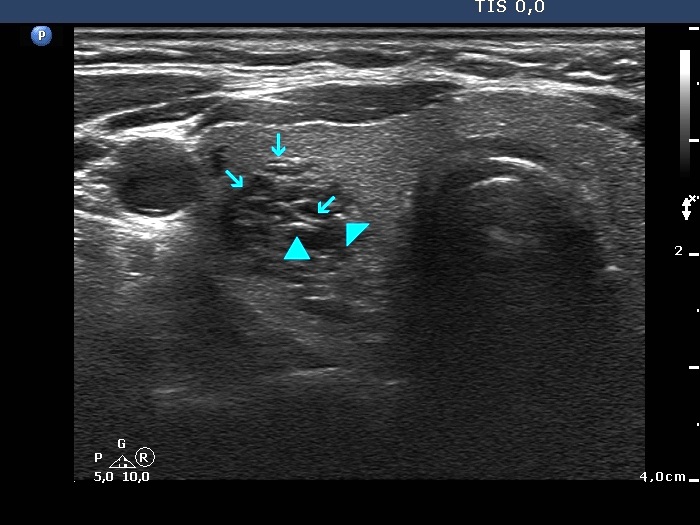

Benign cystic lesion (cytological diagnosis) - case 1139

The posterior acoustic enhancement in the dorsal wall of the small cystic areas causes no concern if this optical artifact is linear (arrows), however granular figures might be misinterpreted as punctate echogenic foci (microcalcifications) (arrowheads).